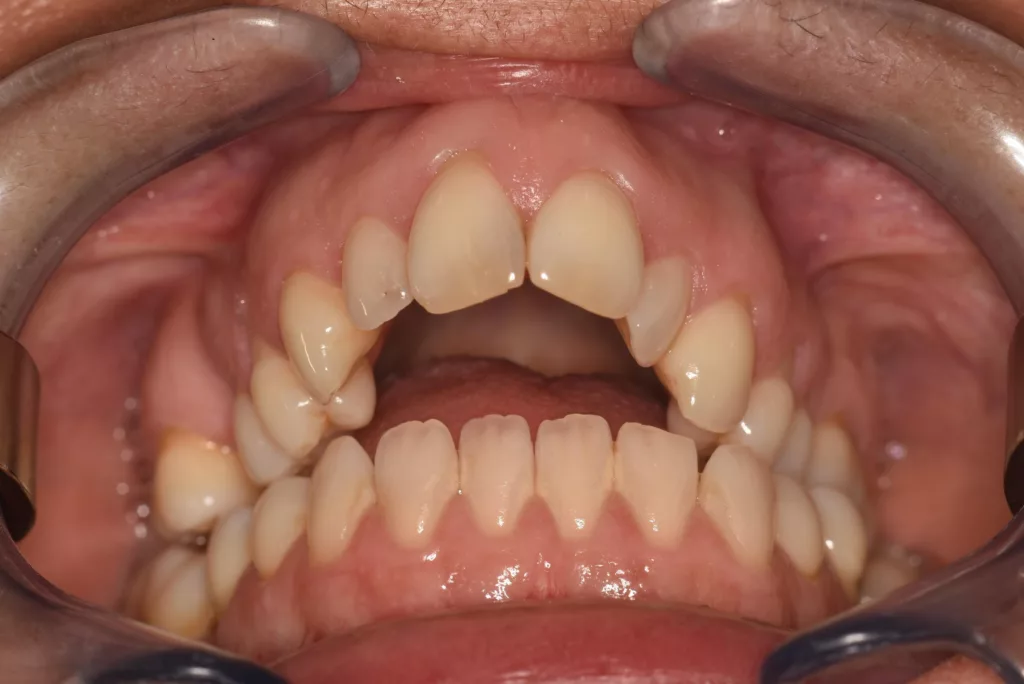

Principales malformations rencontrées : Les Classes III squelettiques

Le maxillaire supérieur est en retrait par rapport à la mandibule. Il peut s’agir d’un manque de développement du maxillaire supérieur et d’une mandibule normale ou au contraire d’un maxillaire normal et d’une mandibule trop développée. Souvent, les deux anomalies se conjurent associant un manque de développement du maxillaire supérieur et excès de développement de la mandibule. On constate souvent une langue en position basse. Le profil facial classiquement observé est « concave » tandis que l’on retrouve fréquemment une occlusion dentaire de classe III. L’appellation courante est le « prognathisme ».

Classe III Squelettique